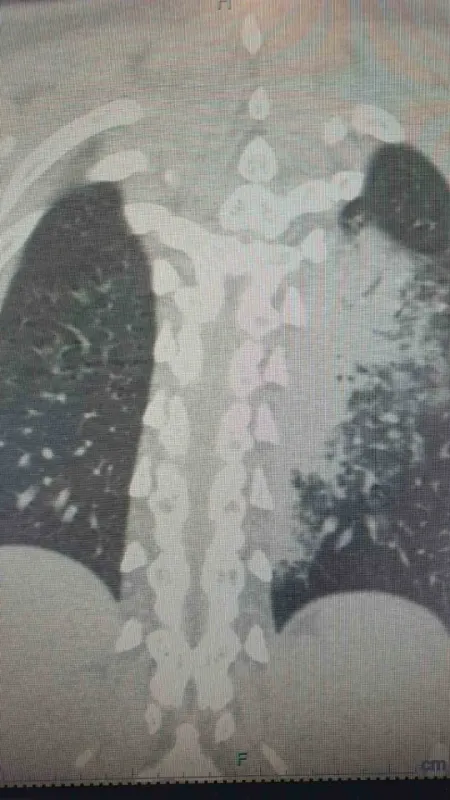

Göğüs Hastalıkları Uzmanı Prof. Dr. Şevket Özkaya, özellikle otel ve tatil köylerinde konaklayan kişiler arasında “beni klima çarptı” diyen neredeyse her iki kişiden birinde bu hastalıkların saptandığını belirtti. Prof. Dr. Özkaya, bu durumdan en çok etkilenenlerin ise çocuk yaş grubu olduğunu vurgulayarak, “Ciddi sayıda, daha önce görülmemiş derecede çocuk bronşiti ve zatürresi vakaları görmeye başladık. Hatta COVID-19 salgınında, çocuk yaş grubunda COVID-19 virüsüne bağlı bu kadar çok zatürre görmüyorduk. Son günlerde; ‘Legionella’ bakterisinin, çocuk yaş grubunda COVID-19’a oranla çok daha fazla zatürreye neden olduğunu görüyoruz” diye konuştu.

Legionella pneumophila isimli bakterinin klimalardan üremesi sonucunda hastalığın ortaya çıktığını belirten Prof. Dr. Özkaya, bu hastalığın kronik rahatsızlığı olanlarda ölümcül olabileceğini ve yaşlı, kronik hastalığı olan vatandaşların dikkatli olmaları gerektiğini hatırlattı.

Prof. Dr. Özkaya bakterinin genellikle ılık sularda kolaylıkla çoğalabileceğini söyleyerek, “Genellikle bir binanın kirlenmiş su dağıtım sistemi yoluyla yayılır. Hastalık havada asılı duran su damlacıklarının solunması yoluyla insanlara bulaşır. Bakteri o kadar küçüktür ki, su buharı gibi küçük su damlacıklarının içine yerleşerek havaya karışabilir. Kontamine suların bulunduğu sauna, hamam veya kaplıca havuzu gibi sıcak sulardan çıkan buhar damlacıklarının solunması ile bakteri akciğerlere ulaşır. Kişiden kişiye yayılım söz konusu değildir” açıklamasında bulundu.

Özellikle klimaların iyi temizlenmesi gerektiğini belirten Prof. Dr. Özkaya, klima zatürresinde şikayetlerin daha az olduğu için grip gibi eklem ağrıları, ateş, halsizlik, ishal gibi hafif soğuk algınlığı belirtileriyle seyrettiği için çok fazla anlaşılmayabileceğini söyledi. Kronik hastalığı olanlarda hayati sonuçlar da doğurabileceğini belirten Özkaya, “Pandeminin bitmesiyle beraber ani ısı değişikliklerine, soğuktan sıcağa geçişlere ve klimalara maruz kalmak, grip ile karıştırılabilir ve önemsenmeyebilir. Çocuklar ise ne hissettiklerini anlatamadıkları için uzamış öksürük ve ateş şikayeti ile doktora başvurduklarında ciddi zatürre vakaları ile karşı karşıya kalırlar” dedi.